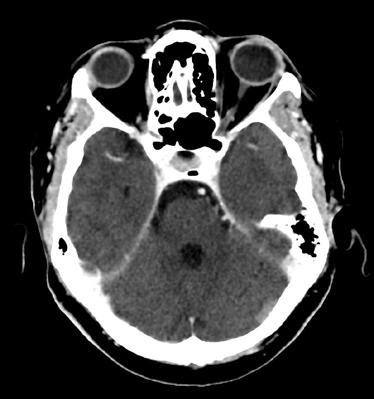

Con la PET/TC eseguita a novembre del 2016 si evidenziava la presenza di significative alterazioni di distribuzione del radiofarmaco a carico del fegato e a livello scheletrico, come da alterazioni di natura sostitutiva. In particolare, in corrispondenza del fegato, si segnalava significativa captazione focale a livello del settimo segmento e altra poco più cranialmente. Si evidenziavano poi plurime significative captazioni estese a tutto il rachide cervicale, dorsale e lombare (SuvMax fino a 18) oltre che a tutto il bacino, oltre che a livello delle coste bilateralmente, clavicola sx, manubrio sternale, entrambe le scapole, entrambe le teste e diafisi prossimali omerali, diafisi omerale destra, entrambi i femori a livello delle teste, delle regioni trocanteriche, maggiormente a sx, diafisi prossimali femorali, corrispettivo alle immagini TC ad alterazioni addensanti, in parte ad alterazioni litiche, in parte a malattia ancora in fase pre-radiologica (figura 1).

1. TC/PET TB, novembre 2016.

Figura